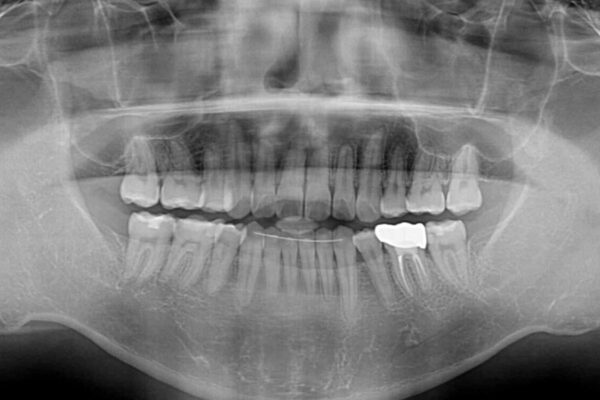

高校時代に行った抜歯矯正が後戻りをしたとのことで来院された患者様です。

治療計画

再矯正であることから、目立ちにくい装置を希望されたため、インビザラインにて矯正治療を行うこととしました。

治療後について

下顎骨が左側に変位しているため、正中が合わないことは予想できましたが、歯列が整った後も咬み合わせが安定せず、咬み合わせを落ち着かせるために1年以上の期間を要しました。

噛みにくさの改善に時間がかかってしまうことがインビザラインの欠点の1つといえます。